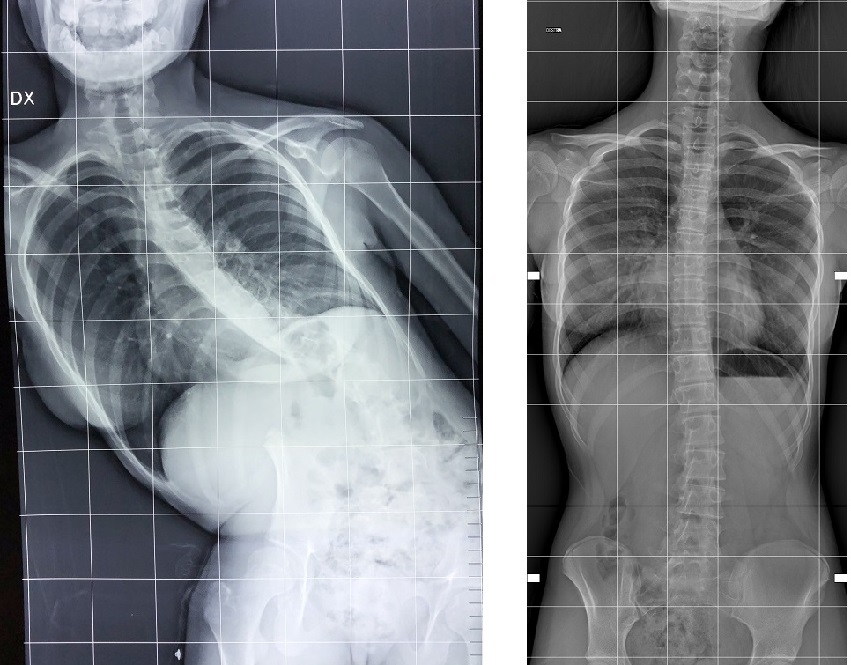

La giovane ragazza di Messina soffriva di una scoliosi antalgica che le impediva non solo una normale deambulazione, ma anche ogni forma di relazione sociale.

È passato più di un anno dall’intervento chirurgico che le ha restituito il sorriso, ma a ripensarci Desirè si commuove ancora. A soli 13 anni la schiena della ragazza, nata e cresciuta a Messina, comincia a curvarsi e, in poche settimane, la scoliosi si fa talmente grave da costringerla ad una postura del tutto innaturale. Una condizione di sofferenza che non le impedisce solo una normale deambulazione, ma anche ogni forma di relazione sociale.

Qui, dopo una prima visita, la ragazza viene presa in carico e seguita dal dottor Angelo Toscano, dirigente medico del reparto di Ortopedia generale specializzato in chirurgia delle deformità del rachide. Toscano comprende subito che la gravità della condizione della ragazza non può essere determinata da una scoliosi primitiva. Ci deve essere qualcos’altro, una causa nascosta che costringe Desirè in quella posizione innaturale. Dopo accurate indagini diagnostiche emerge il sospetto di un’ernia del disco a livello lombare, confermata anche da una risonanza magnetica. Evento rarissimo per una ragazza di soli 13 anni ma che, secondo il team del Dipartimento Rizzoli-Sicilia di Bagheria, è certamente la causa che ha scatenato una così grave condizione. Si tratta di una scoliosi secondaria, bisogna intervenire chirurgicamente.